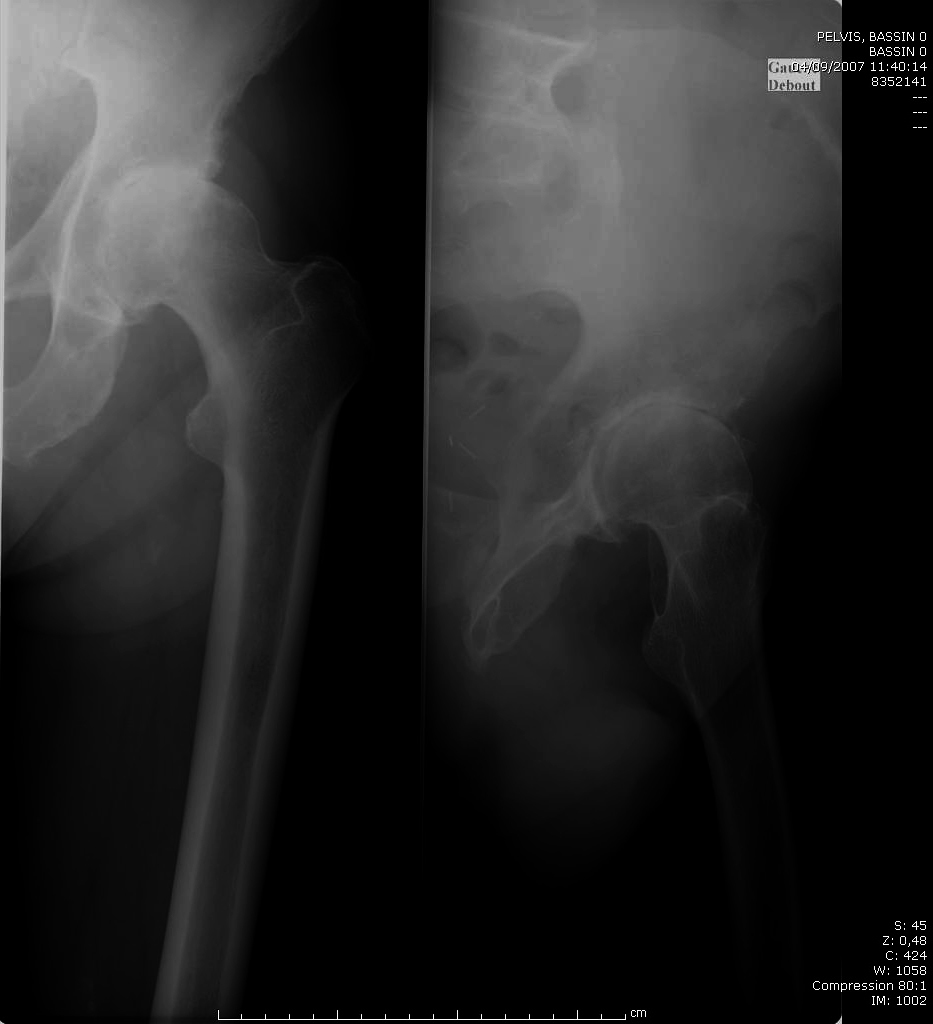

Monsieur M. vous rapporte une plainte au niveau de sa hanche gauche. Initialement ses douleurs étaient simplement à type de gêne, apparues il y a deux ans, sans traumatisme évident à l’anamnèse. Actuellement ces douleurs peuvent le maintenir alité les mauvais jours. Au réveil, il doit patienter quelques minutes assis avant de se lever, avec nécessité de se « dérouiller » avant de pouvoir « s’activer ». Parlant justement du sommeil, sa femme vous dit que cette douleur le réveille souvent lorsqu’il se retourne dans le lit. Il sort de moins en moins, ne peut plus jardiner et est devenu dépendant de son épouse pour les trajets, la conduite lui étant devenue impossible. Vous estimez son périmètre de marche à quelques centaines de mètres, les douleurs apparaissant très rapidement à la marche.